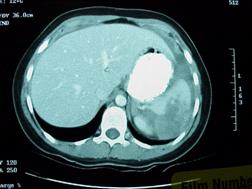

Traumatism

abdominal inchis Traumatism

abdominal inchis

Leziune de splina Leziune de splina